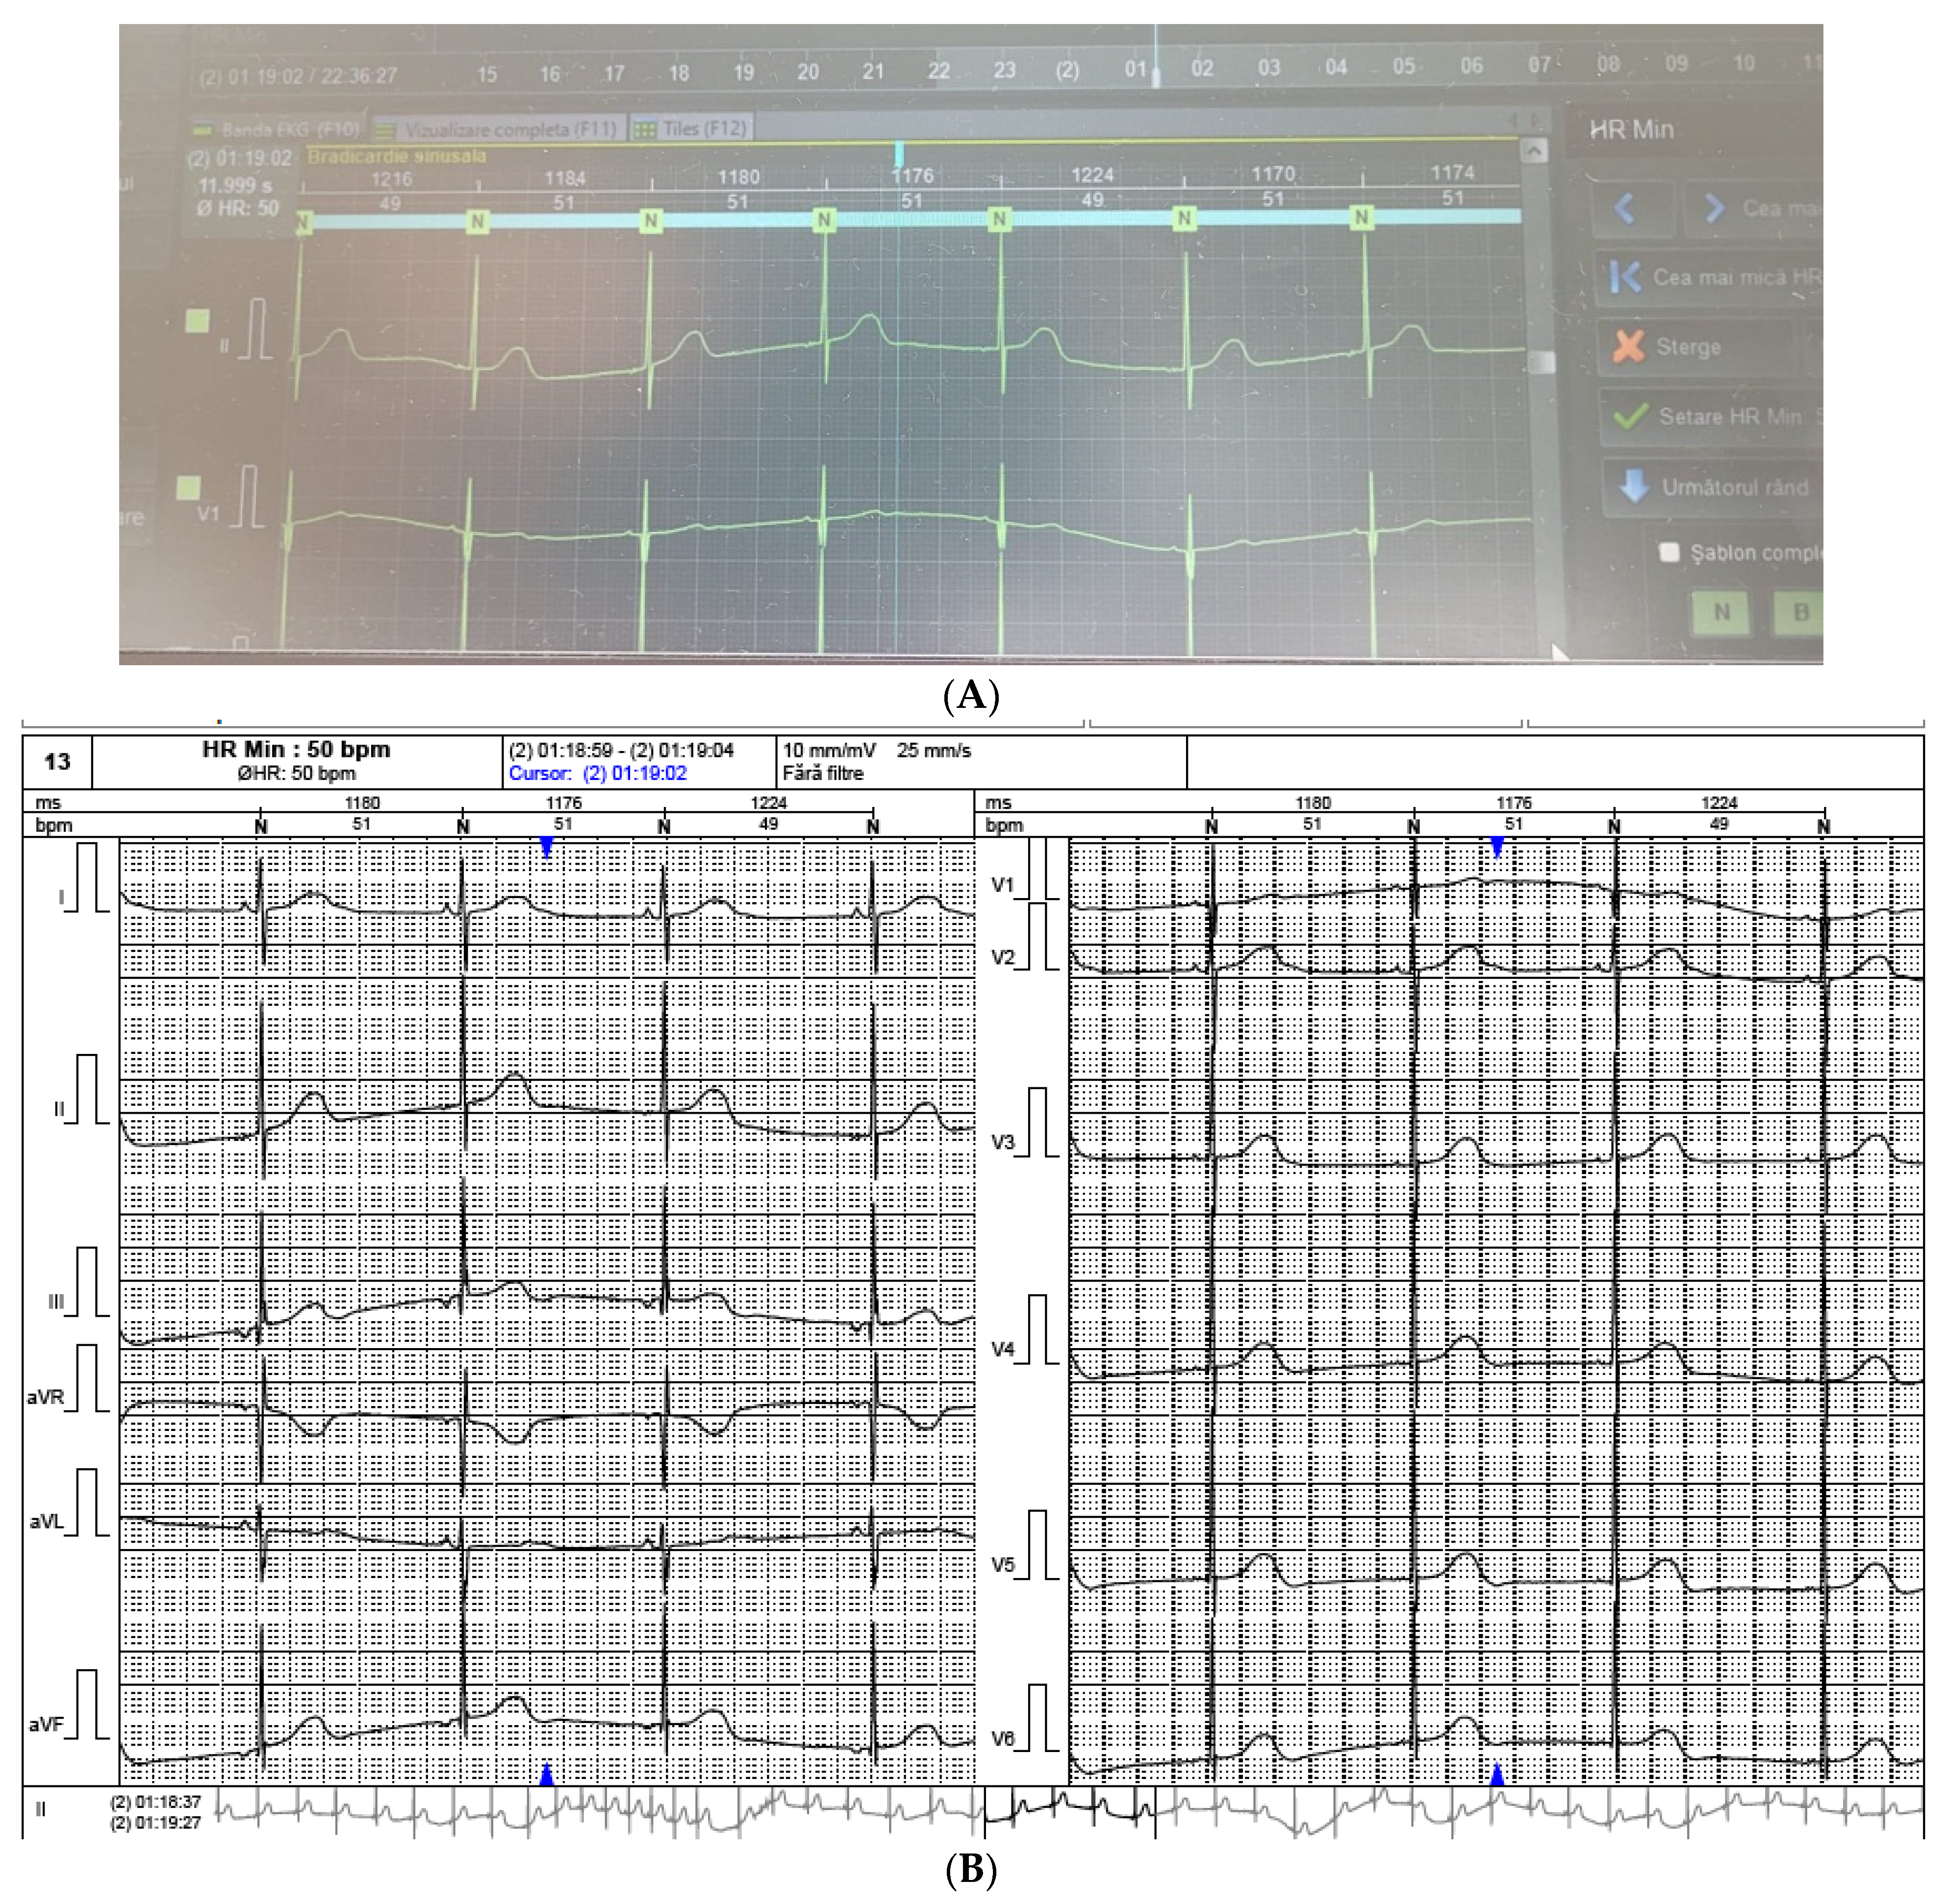

2. Case Report